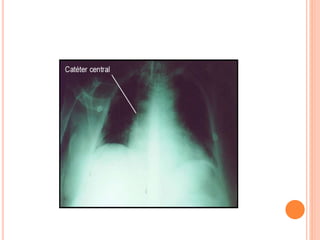

 Após inserção, é realizado RX para confirmar a

posição do catéter e possíveis complicações como

pneumotórax.

CATETERIZAÇÃO DA ARTÉRIAPULMONAR  A inserção do catéter é um procedimento estéril, médico, sendo as veias de escolha a jugular interna e a subclávia.  Após inserção, é realizado RX para confirmar a posição do catéter e possíveis complicações como pneumotórax.  É essencial que o paciente seja monitorado com ECG durante a inserção e manutenção do CAP. Equipamentos pra RCP e desfibrilação devem estar prontamente disponíveis.